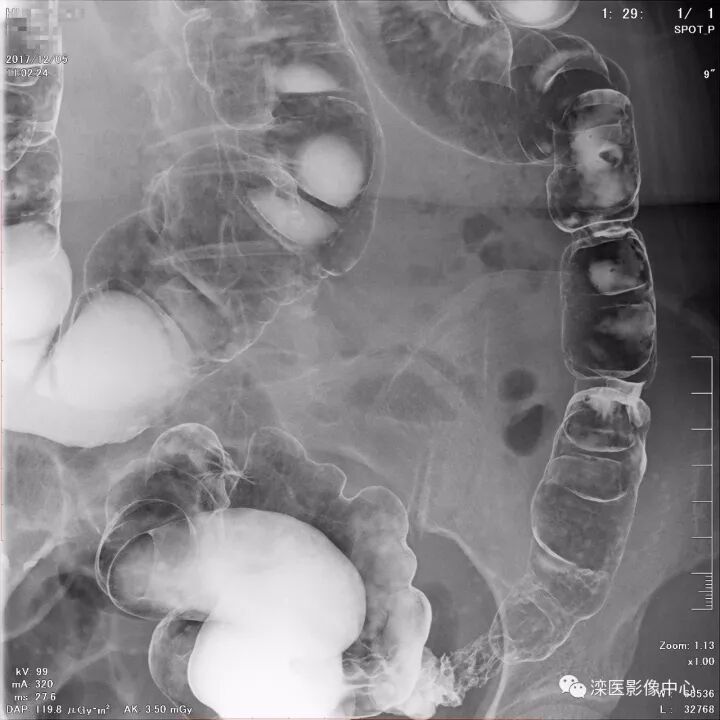

下面请您审阅近期我院影像科开展下消化道双对比造影检查的图像:

(以上图像是对结肠脾曲、横结肠、结肠肝曲的显示)